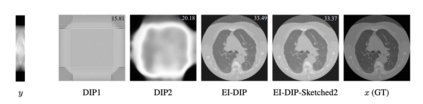

Equivariant Imaging (EI) regularization has become the de-facto technique for unsupervised training of deep imaging networks, without any need of ground-truth data. Observing that the EI-based unsupervised training paradigm currently has significant computational redundancy leading to inefficiency in high-dimensional applications, we propose a sketched EI regularization which leverages the randomized sketching techniques for acceleration. We then extend our sketched EI regularization to develop an accelerated deep internal learning framework -- Sketched Equivariant Deep Image Prior (Sk.EI-DIP), which can be efficiently applied for single-image and task-adapted reconstruction. Our numerical study on X-ray CT image reconstruction tasks demonstrate that our approach can achieve order-of-magnitude computational acceleration over standard EI-based counterpart in single-input setting, and network adaptation at test time.